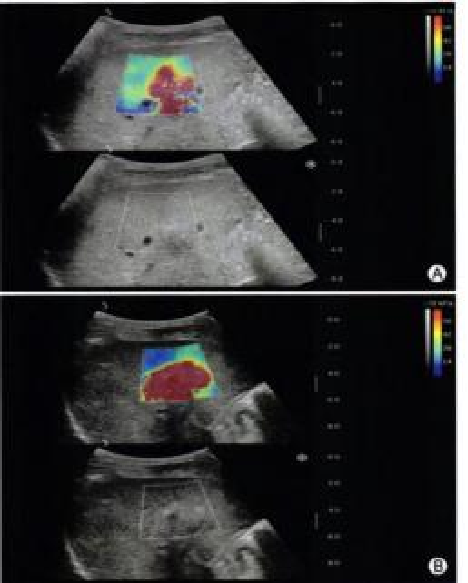

声速定量成像

作为一种新兴的超声成像技术,为医学诊断和生物医学研究提供了重要的信息。利用声波在不同组织中的传播速度差异,测量每个部位的声速,并将测出来的声速通过彩色编码进行显示,生成反映组织物理特性的图像(即声速成像图),对于疾病的早期检测、诊断和治疗评估具有重要的意义。

声速定量成像给临床提供了全新的诊疗思路及工具。

image.png